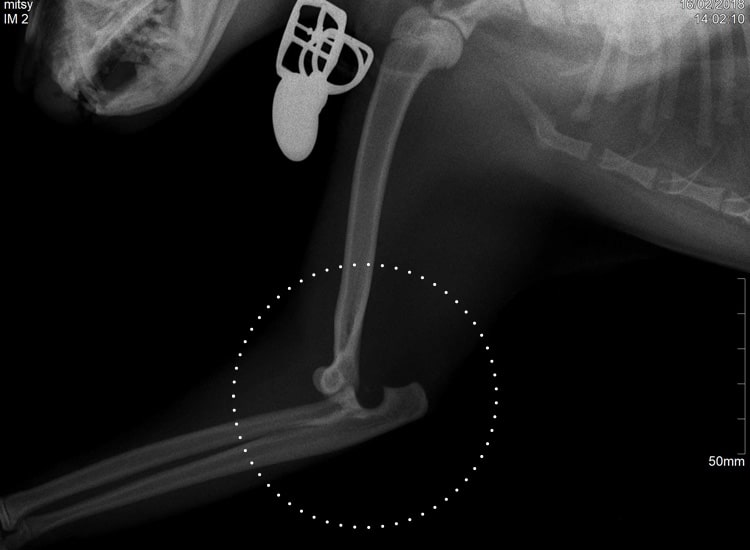

Luxation du coude chez le chat

La luxation du coude est plus rare chez le chat et causée en général par un traumatisme. Mais il arrive également d’observer des luxations congénitales.

La réduction manuelle est efficace lorsqu’elle est réalisée précocement.

Radiographie d’une luxation du coude chez un chat